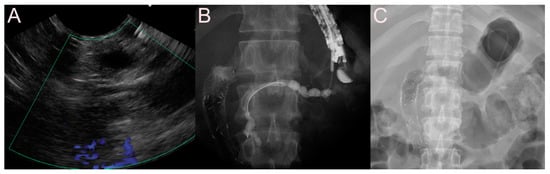

2.1. Stent for EUS-Guided Peripancreatic Fluid Collection (PFC) Drainage

2.1.1. Use of the Plastic Stent

2.1.2. Use of the Self-Expandable Metal Stent (SEMS)

2.1.3. Use of the Lumen-Apposing Metal Stent (LAMS)